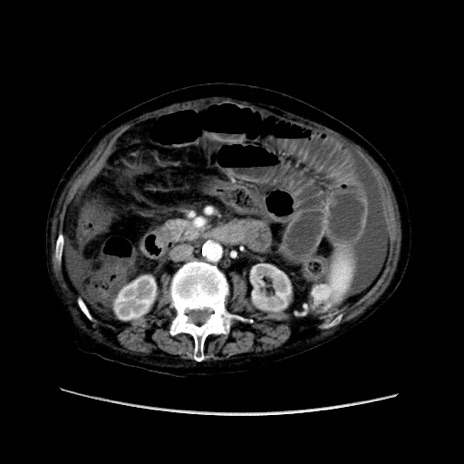

症例31(横断像)

【症例】80歳代 女性

【主訴】腹部膨満感

【現病歴】他院にて肝硬変にてフォロー中。1週間前から便秘、腹部膨満感、臍部腫瘤あり受診となる。

【既往歴】肝硬変

【身体所見】腹部膨隆あり、皮膚変化なし、疼痛なし。

【データ】WBC 4600、CRP 0.25